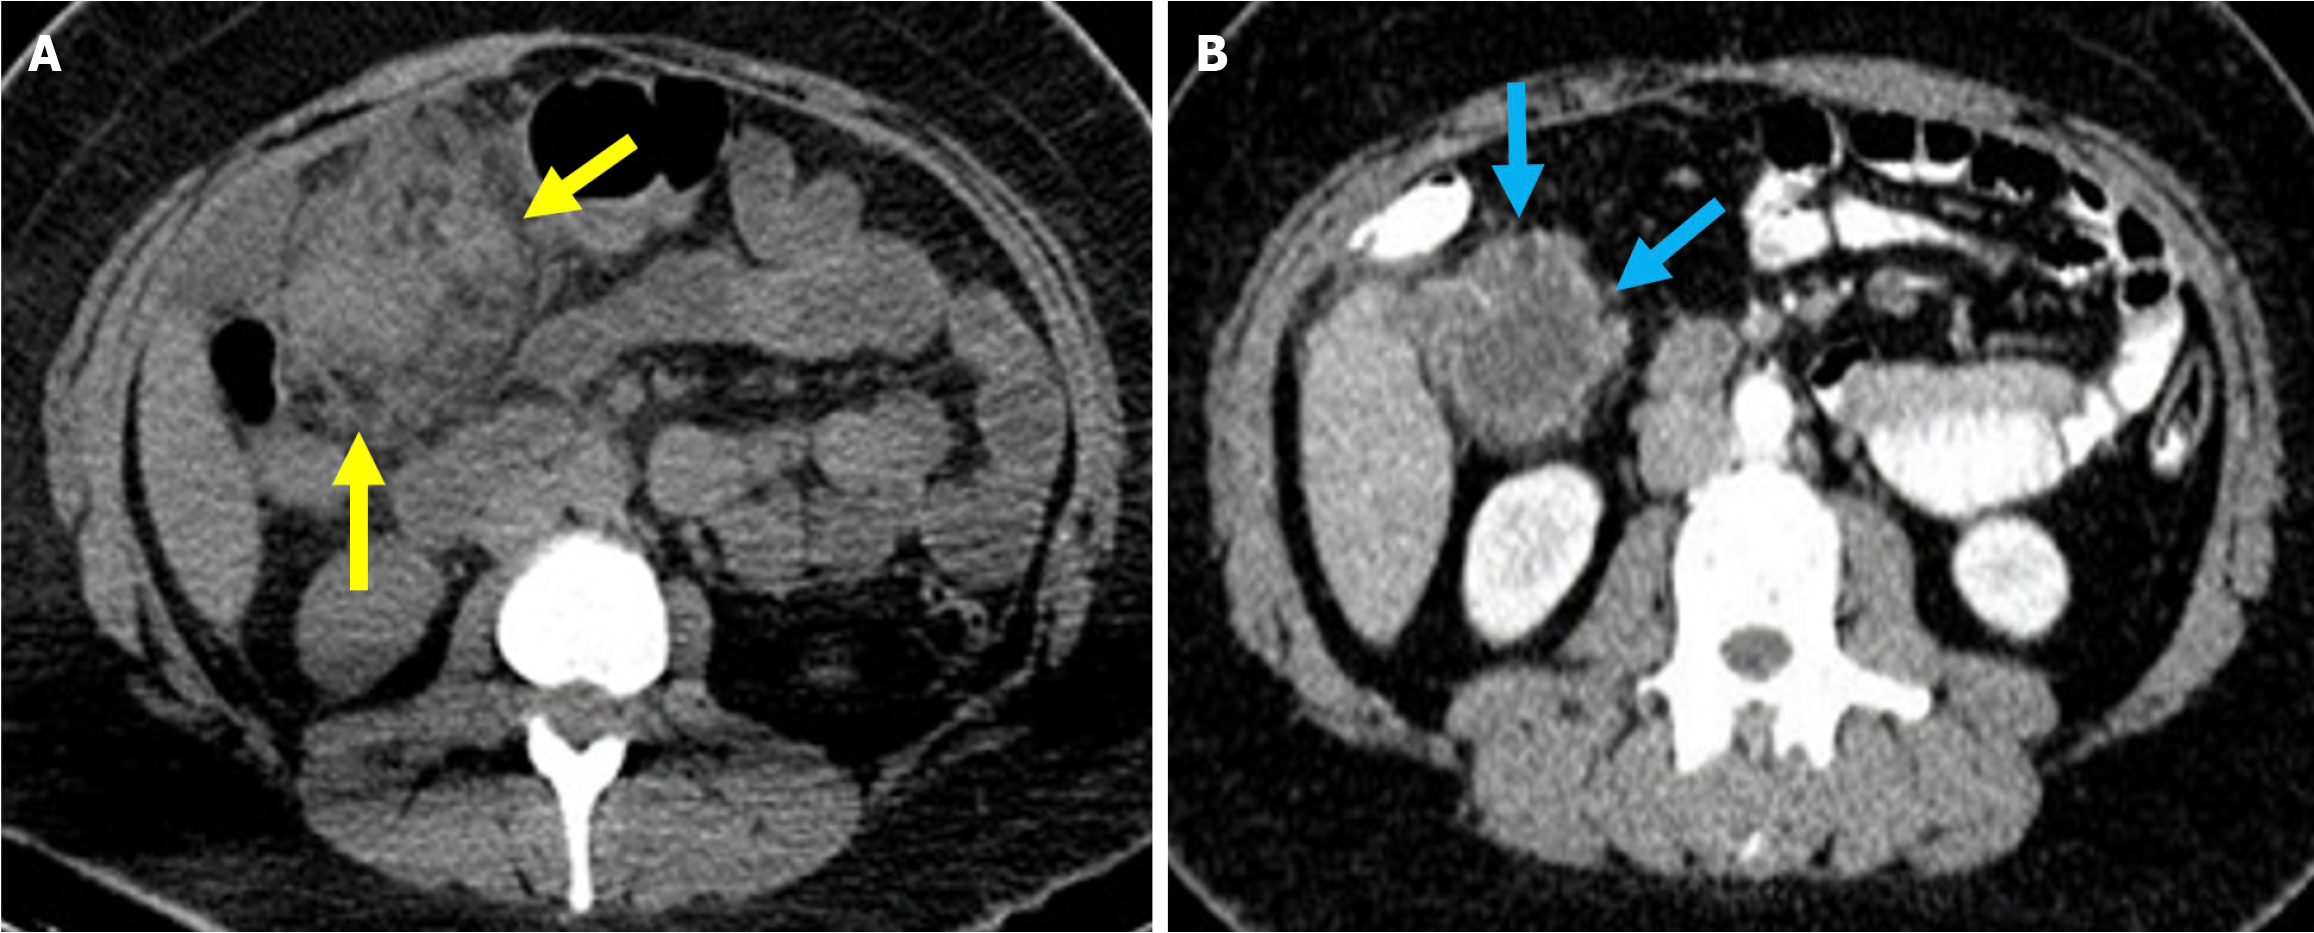

Acute duodenal wall hemorrhage appears as an area of high-attenuation wall thickening on imaging. The attenuation decreases as the hemorrhage evolves and often forms a pseudocapsule. Hyperattenuating blood can be seen within the CBD and the duodenal lumen in cases of intraluminal bleeding. Arterial phase acquisition with vascular window settings and maximum intensity projection reconstruction demonstrate active contrast extravasation in the duodenum (Figures 9 and 10)[37,61,62].

Figure 9

Figure 9 Acute duodenal wall and mesenteric hemorrhages. A and B: Axial (A) and coronal (B) noncontrast computed tomography images revealed findings consistent with hemorrhage in an 81-year-old female patient who presented with abdominal pain and a drop in hemoglobin levels following endoscopic retrograde cholangiopancreatography. A high-density mesenteric collection and mesenteric fat stranding were observed and consistent with mesenteric hematoma (blue arrows). Hyperattenuating duodenal wall thickening, indicative of an intramural hematoma (orange arrows), was also present. Free fluid was noted in the perihepatic space (yellow arrow).